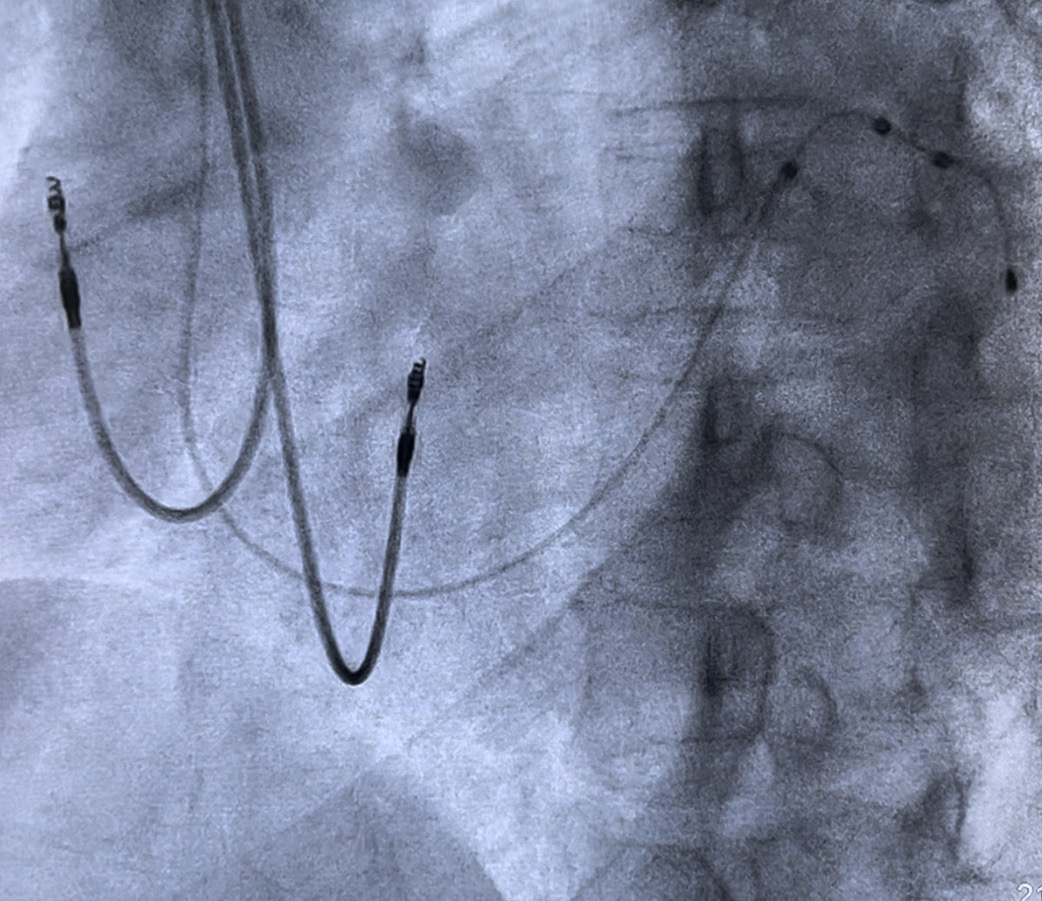

CRT Implant Procedure

Implanting the CRT is similar to pacemaker insertion and the two procedures share many common risks and considerations. CRT, however, is a longer and more challenging procedure as three leads have to be inserted inside the heart instead of two as in a routine pacemaker.

One of the leads enters the left side of the heart via a small vein called the coronary sinus. The anatomy of the coronary sinus and its branches is often the rate-limiting step in a CRT implant. A favourable anatomy will result in a very easy procedure, while an unfavourable anatomy will result in a longer, more complex one.

Generally, in >90% of cases, a successful CRT implant can be achieved. Like pacemaker implantation, the complication rate remains low.